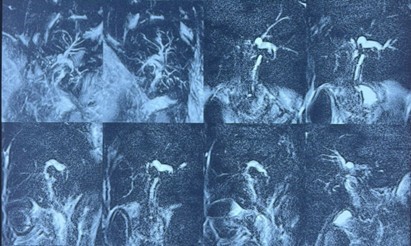

No calcified opacity was identified projecting over the hepatic area. Surgical drainage tubes were visualized in the subhepatic region. Digestive gas was present.

Following opacification with iodinated contrast medium injected through the Kehr T-tube, the T-tube was confirmed to be in place. Mild dilatation of the proximal right and left intrahepatic bile ducts was observed, containing a few filling defects consistent with aerobilia. There was slight dilatation of the common bile duct, without any clearly identifiable obstructive lesion. The gallbladder and cystic duct were not visualized. Contrast medium passed freely into the duodenum, with no evidence of contrast extravasation.

Figure 4: T-tube cholangiography demonstrating adequate opacification of the biliary tree with free passage of contrast into the duodenum, but without visualization of the gallbladder. Dilated common bile duct with visualization of the Kehr T-tube (green arrow) and the duodenum (blue arrow).